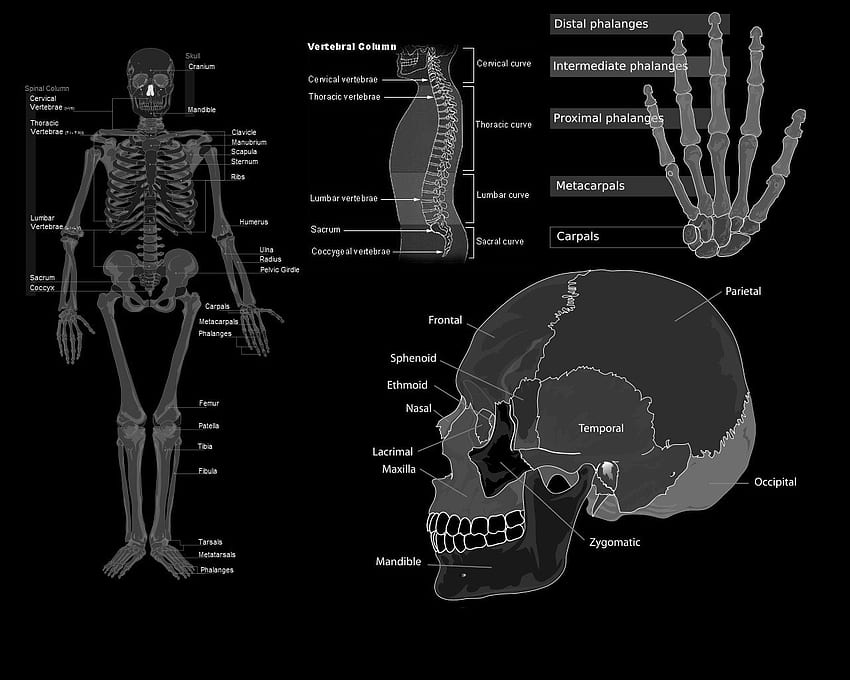

www.ebth.comAnatomy Background, Vintage Anatomy HD Wallpaper | Pxfuel

www.ebth.comAnatomy Background, Vintage Anatomy HD Wallpaper | Pxfuel

www.greatbigcanvas.comAmazon.com: 16” X 20” Vintage Anatomy Print Human Skeleton Diagram

www.greatbigcanvas.comAmazon.com: 16” X 20” Vintage Anatomy Print Human Skeleton Diagram

www.amazon.comanatomy vintage human poster skeleton amazon reproduction diagram flash player video